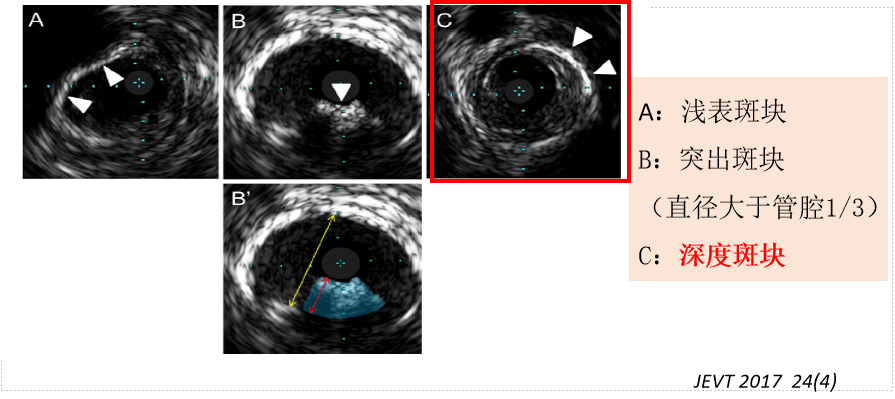

IVUS下“钙化斑块”位置

严重股腘动脉钙化斑块:如何处理斑块?